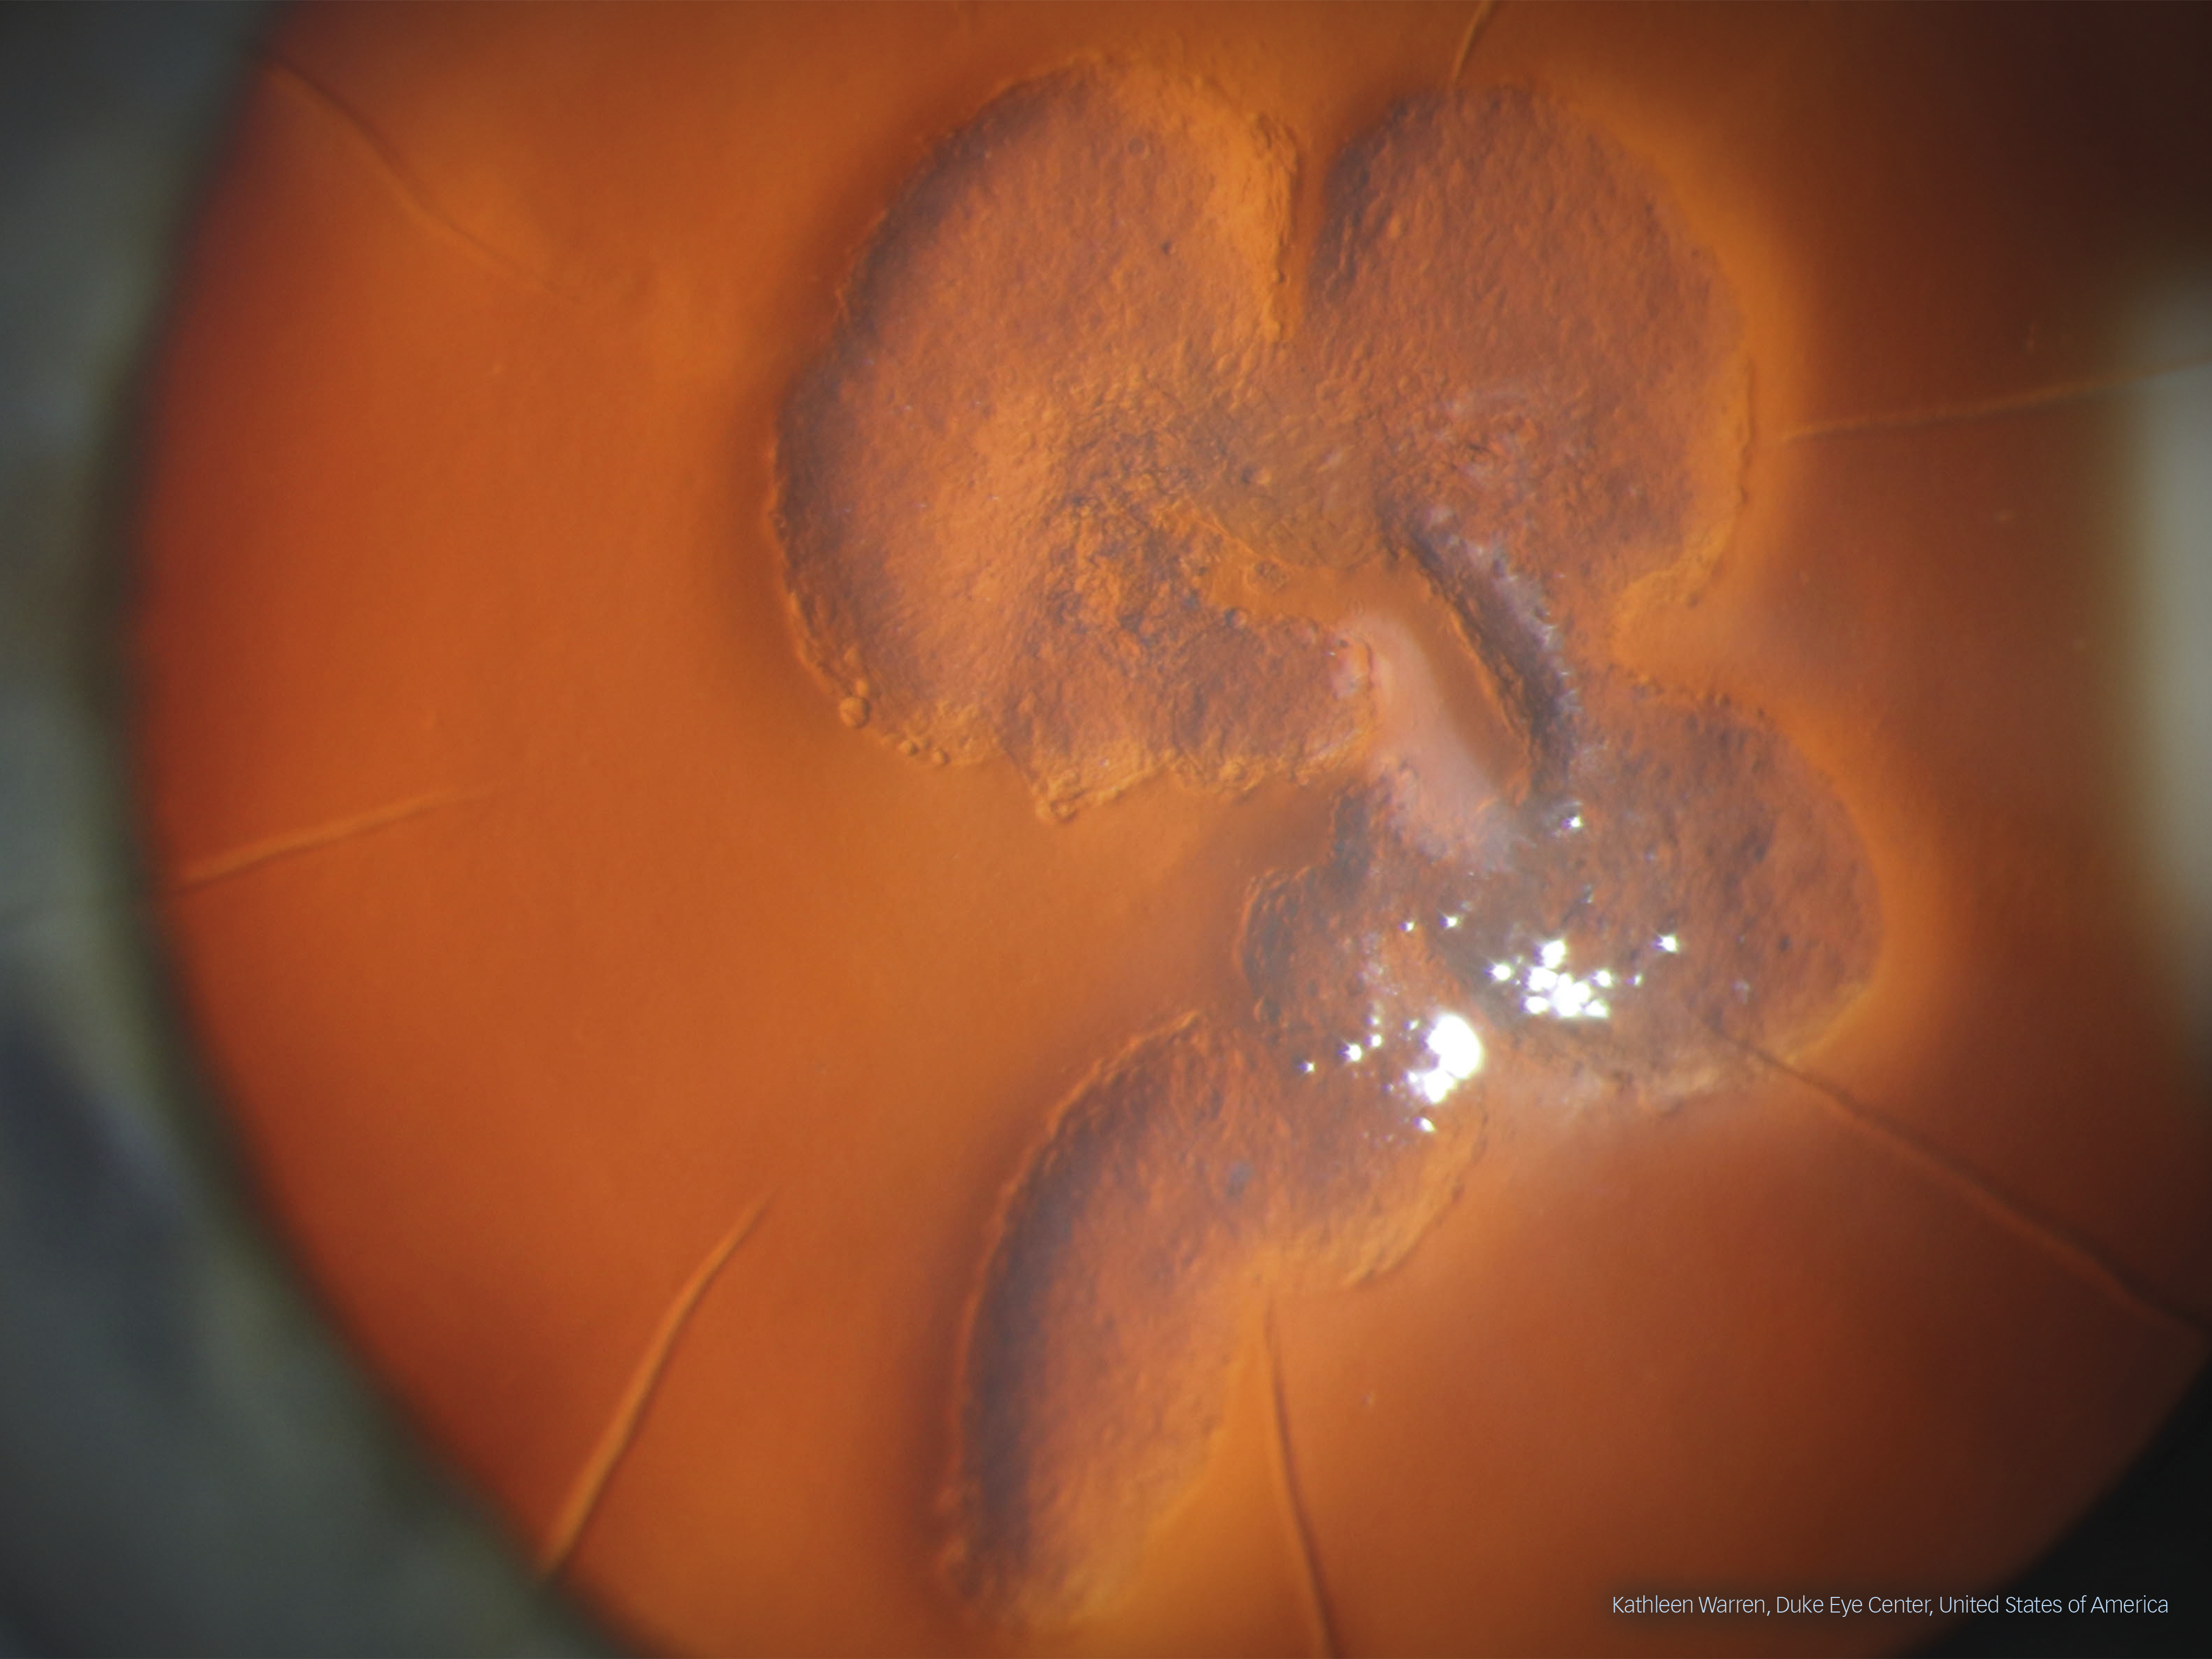

Third prize, a Peak Design Everyday Backpack, was awarded to Kathleen Warren from Duke Eye Center, Durham, North Carolina, USA. Her winning image displays a case of epithelial in-growth, taken with a Haag-Streit BX 900 slit lamp. Captured with large magnification, the image was described as “not only detail rich and fully in focus, but it has also been chosen for its artistic qualities”.

A case of epithelial in-growth by Elizabeth Warren